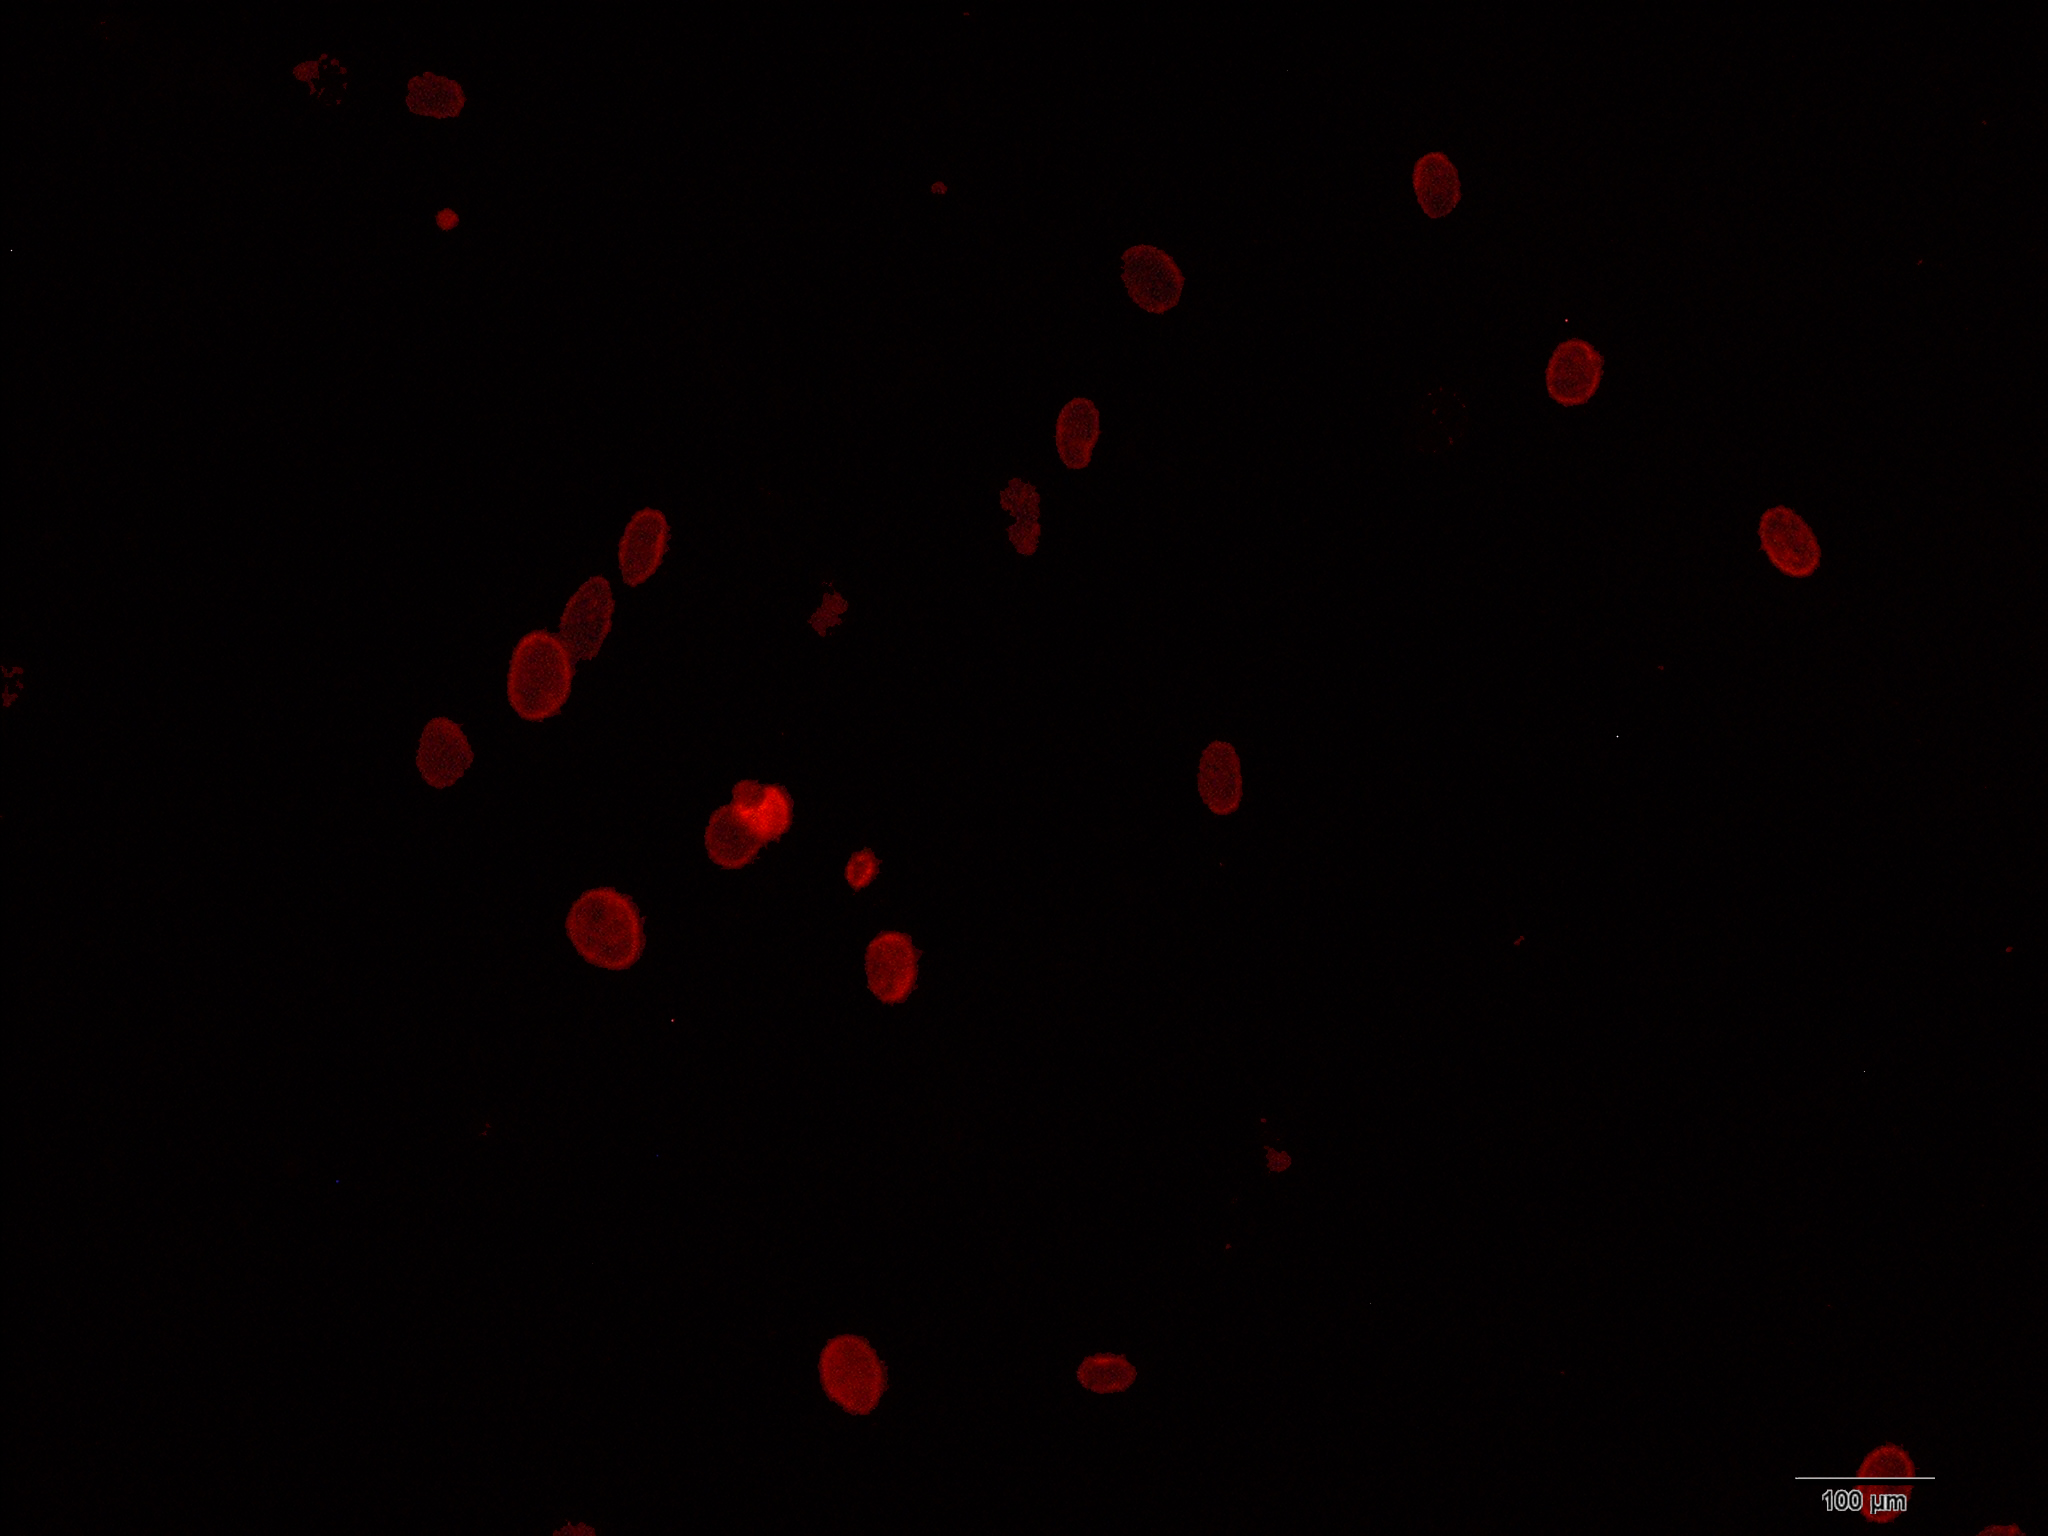

Figure 2 of Li, Mol Vis 2010; 16:2739-2744.

Figure 2. Immunofluorescence staining of 63-kDa protein in primary culture of mouse limbal epithelial cells. The 63-kDa protein positive cells (red) indicated the presence of the limbal epithelial progenitor cells.